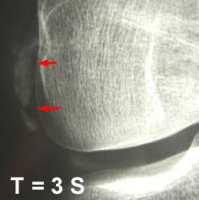

Aspect Radiologique : reflète la durée de la maladie

- stade de début,  les cristaux apparaissent mal définis et nuageux,

- avec la progression de la maladie, ils apparaissent plus denses et homogènes avec une configuration linéaire ou circulaire.